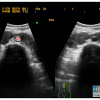

– Thận xoa trục, 2 cực dưới thận liên tục với nhau vắt ngang qua phía trước cột sống bởi nhu mô thận hay tổ chức xơ.

– Trên lát cắt dọc: không thấy rõ ranh giới cực dưới 2 thận.

– Trên lát cắt ngang qua đường giữa: 2 thận dính nhau, vắt ngang qua cột sống, phía trước động mạch chủ bụng.

– Có thể kèm theo các bất thường bất thường đường bài xuất, thận đôi, sỏi, nang thận hoặc u thận, sỏi gây giãn đường bài xuất.

=> Case lâm sàng 1: